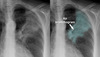

What is the red arrow indicating?

Is this a normal finding on a CXR?

A

• Gastric bubble

• This is a normal finding on a CXR

Free air: Instead of the air being contained inside the stomach to the unitlateral side of the diaphgram, air will be displaced bilaterally on both sides of the diaphragm.